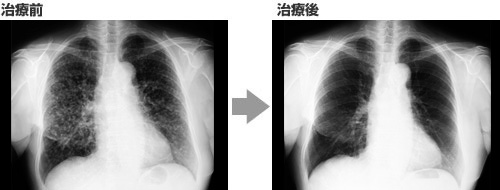

本書掲載の改善症例のCT画像をご紹介

肺がん